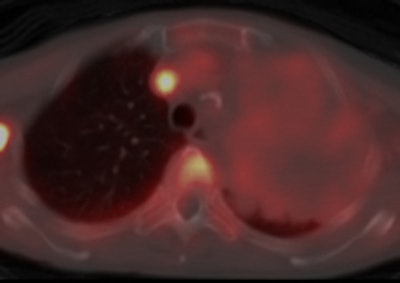

Amount of docetaxel uptake in tumors

An example of a patient with non-small cell lung cancer showing relatively high C-11 docetaxel uptake in a tumor with a volume of 334 cm3. During the therapeutic scan, the patient was treated with 110 mg of docetaxel. Left: CT scan showing tumor. Right: PET/CT fusion image of a therapeutic C-11 docetaxel summed image [25-65 min; mean C-11 docetaxel Ki = 0.0125 mL·cm-3·min-1; total accumulated amount of cold docetaxel at 90 min = 543 µg (at 1.62 µg·cm-3), corresponding with 0.49% of the infused dose docetaxel]. Images courtesy of Dr. Astrid van der Veldt, PhD.A potential problem was that the behavior of 11-C docetaxel in the tumor at tracer doses may be different from its behavior at therapeutic doses, noted van der Veldt. Therefore, she investigated whether a PET study using tracer doses of C-11 docetaxel could predict tumor uptake of docetaxel at therapeutic doses.